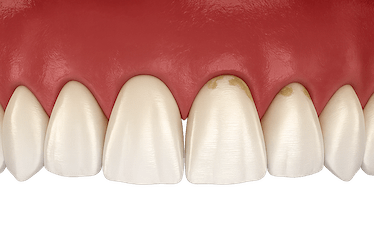

- Sangrado de encías: se produce especialmente al cepillar los dientes o al usar el hilo dental, indicando que hay algo que no marcha bien.

- Encías inflamadas o con alteraciones de color: es otro claro síntoma de que hay enfermedad periodontal. Pueden hincharse y ponerse tanto de color rojo brillante como de un tono más oscuro.